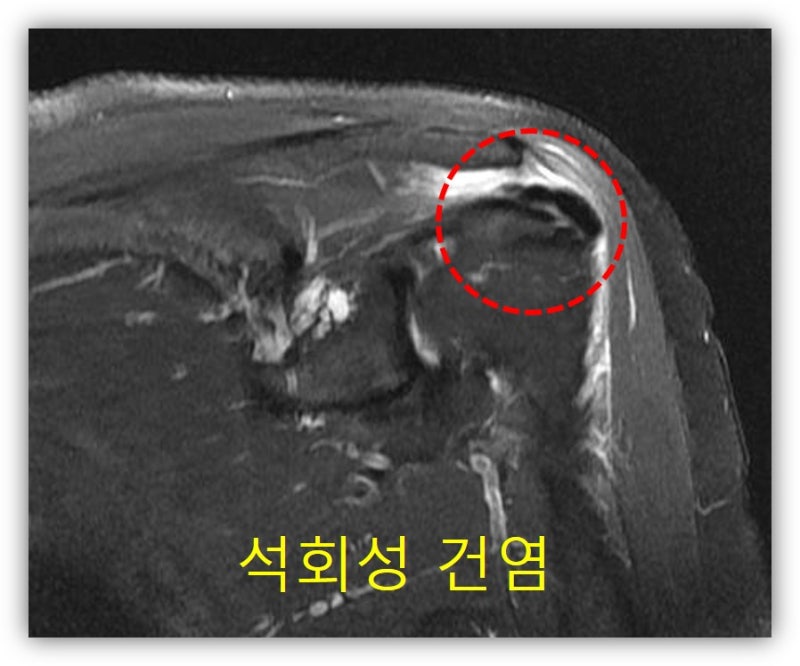

석회가 아주 큰 경우, 그리고 오래된 경우 회전근개의 손상이 있을 가능성이 있어 MRI 검사도 시행하였습니다.

석회성 건염을 오래 앓다 보니 관절낭의 구축까지 있어 가동범위 제한도 심하게 있었습니다. 환자에게 뉴핌스 치료를 시행하였습니다. 관절낭의 구축을 풀어주고 석회분쇄흡입술을 시행하였습니다.